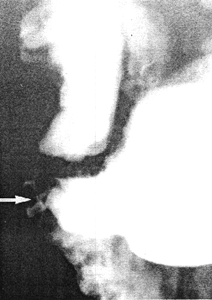

Case 21.1. D.J., 22 year old male, had a long history of dyspepsia not responding to anti-ulcer treatment. Two days before admission there had been an episode of haematemesis. Gastroscopy showed a small orifice on the posterior gastric wall close to the pyloric aperture. It was thought to be either an intramural diverticulum or a double pylorus; radiographic examination was requested for further elucidation. This showed a small, branching, diverticular structure approximately 1.0 cm in length, on the greater curvature side of the pyloric sphincteric cylinder within 1.0 cm of the pylorus (Fig. 21.1). It remained constant in appearance irrespective of the degree of contraction of the cylinder, the contractions being normal. At laparotomy no evidence of ulceration was seen. A nodule of abnormal tissue measuring approximately 2.0 cm in diameter was palpated in the gastric wall at the site indicated by endoscopy and radiology. Gastrostomy revealed a small orifice extending into the nodule, which was removed by local excision. Histology showed it to consist of endo- and exocrine pancreatic tissue located in the muscular coat of the stomach.

Fig. 21.1. Case D.J. Small, branching, diverticulum-like structure (arrow) on greater curvature side of pyloric sphincteric cylinder |

In this case a small nodule of ectopic pancreatic tissue in the wall of the greater curvature of the pyloric sphincteric cylinder did not affect the movements of the cylinder to any appreciable extent. Radiographically the lesion mimicked an intramural diverticulum (Chap. 22).